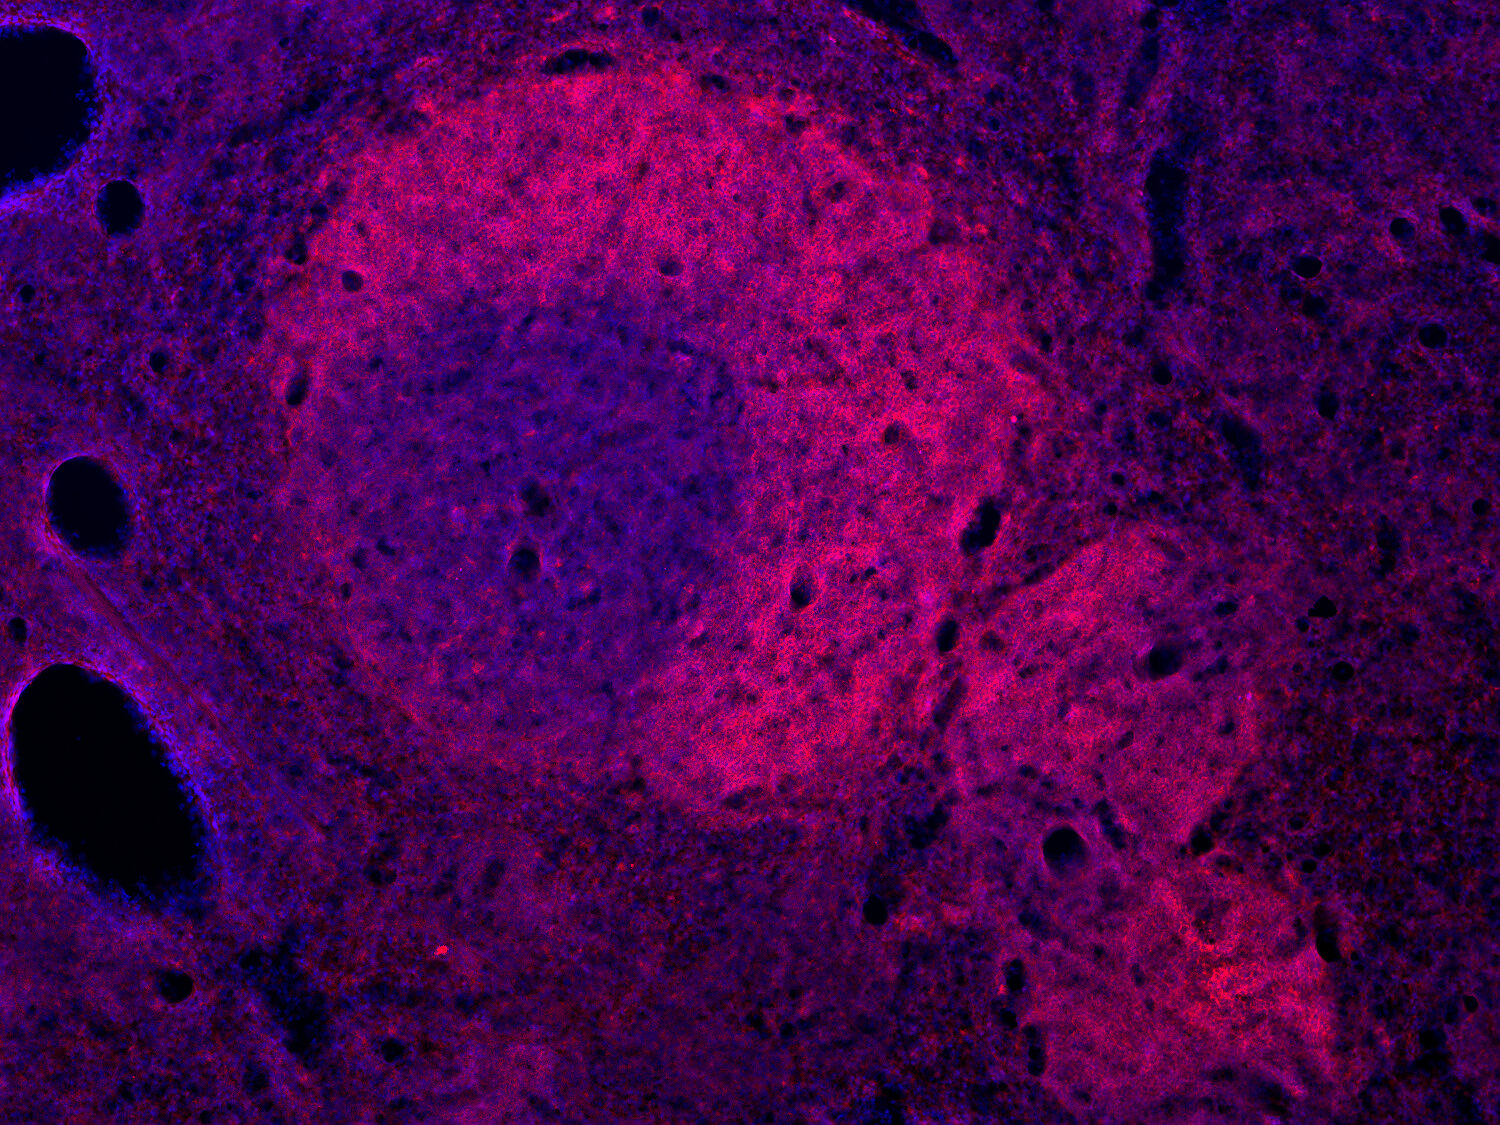

Fluorescent double staining for CD19 (red) and CD3e (green) visualizes B-cell and T-cell populations in the mouse spleen